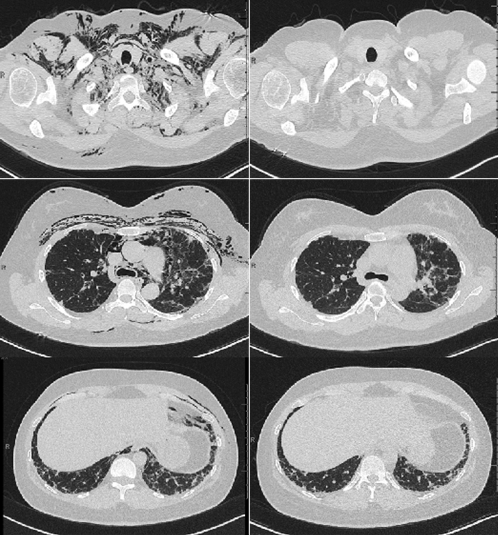

A 35-year-old female with interstitial lung disease due to anti-synthetase syndrome presented with cough, hoarseness and facial swelling. Chest computed tomography scan demonstrated significant pneumomediastinum (Figure 1). Bronchoscopy and esophagram were unremarkable. We began high-concentration oxygen (10 L/min with non-rebreather face mask for 12-hours/day), withheld mycophenolate mofetil, reduced prednisone and began dextromethorphan. After one-month, there was complete resolution of her symptoms and pneumomediastinum.

Figure 1: Chest computed tomography (CT) scan at the level of the neck, heart and lung base demonstrating subcutaneous air and pneumomediastinum (left). After one-month of high-concentration oxygen, anti-tussives and reduction in immunosuppression; there was complete resolution (right).